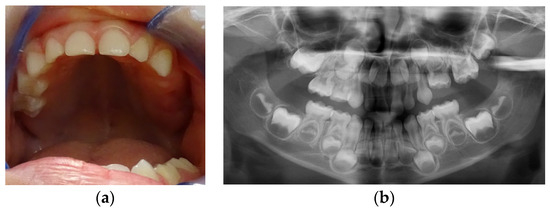

At the age of 12 y and 11 m, while the upper canines were erupting, the clinical and radiological situation in the distal part of the upper left quadrant was not much different from before (Figure 8a–c).

Figure 8.

Age of 12 y and 11 m. Intraoral pictures (a,b) and panoramic X-rays (c) showed retained 26 and 27.